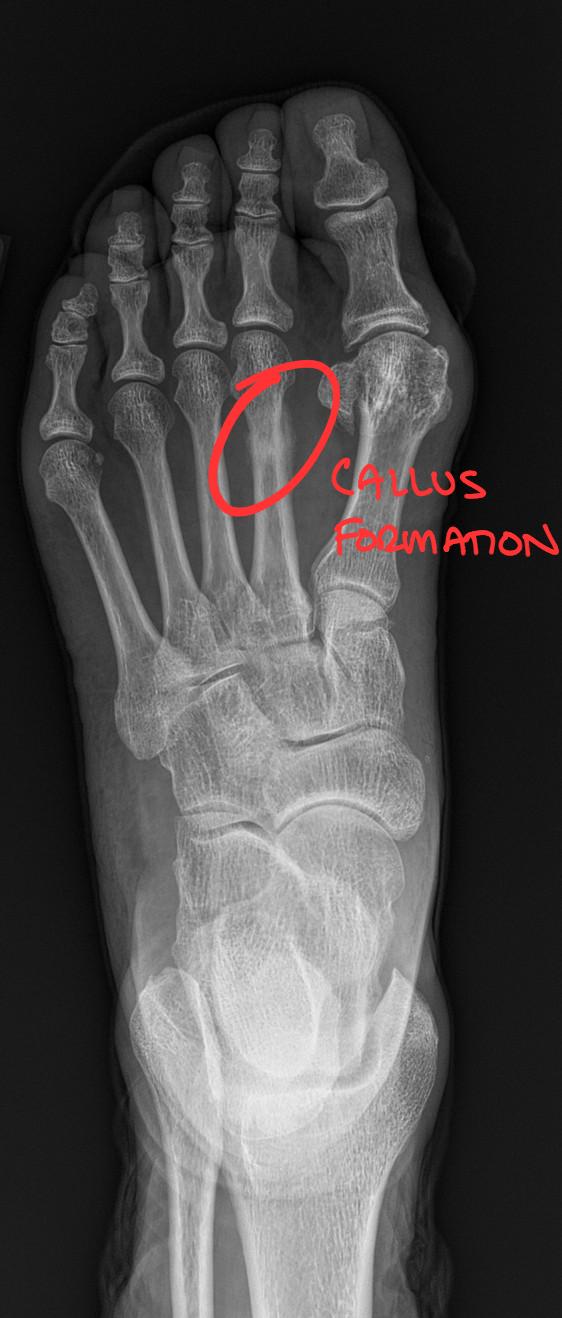

Second Metatarsal Stress Fracture: Diagnostic Imaging Consultants Guide to X-ray and MRI Findings

Second Metatarsal Stress Fracture: Diagnostic Imaging Consultants Guide to X-ray and MRI Findings Key Takeaways The “Silent” Fracture: Stress fractures